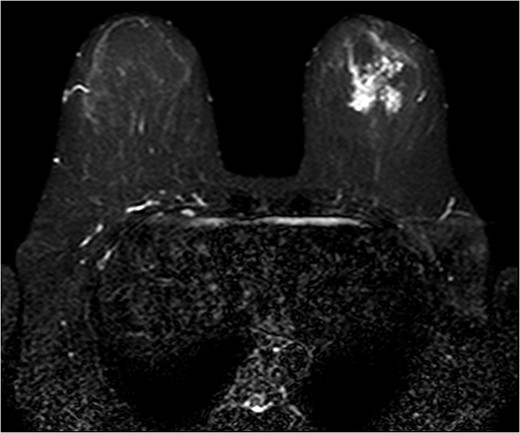

The patient was then sent for MRI of the breast to detail the extent of the remaining mass. This revealed an ill-defined mixed linear and fine nodular enhancing tumor 6.5 × 4.6 × 4.8 cm in size with BI-RADS 5 (Figs 4–7).

The role of MRI in identifying the extent of breast carcinoma is widely reviewed. EPC has been noted to have multifocal hyperintensities at T1 weighted imaging. Contrast MRI will reveal enhancement of the cystic wall, septa and mural nodules [4].